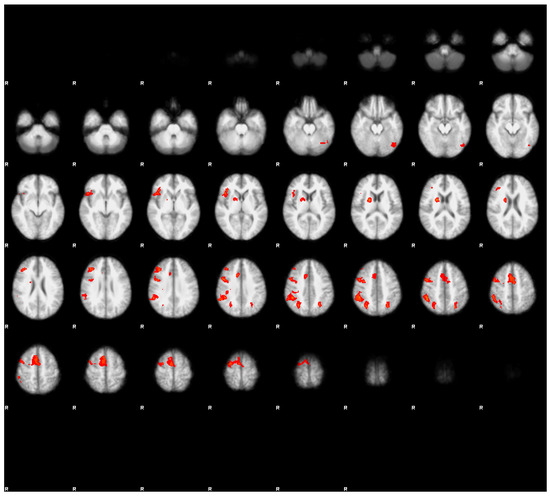

3.3.2. Contrast Results

Direct contrast between both conditions revealed a suprathreshold cluster only in the contrast fatigued > rested. The cluster was located in the right superior frontal gyrus (see Figure 4c). Interestingly, this region did not exceed the Z = 3.1 threshold in either condition, and it appeared in the fatigued > rested contrast because of the negative Z values in the rested condition (see Figure 4a showing the unthresholded Z values) and positive Z values in the fatigued condition (Figure 4b shows the unthresholded Z values). Thus, the difference of activation of this region in both conditions was caused by low response of this region in the rested condition and the moderately elevated response in the fatigued condition.

However, at the same time we observed a notable decrease of the extent of activation in the fatigued condition, indicating a less-consistent brain response to the experimental task across participants. Interestingly, we observed a more lateralized pattern of activation in the fatigued condition, with the majority of clusters located within the right hemisphere. We surmised that this effect might be associated with lowered brain metabolism in the state of sleep deprivation [22]. Of course, this does not mean that truck driver’s brain resembles a brain of a dolphin, yet it points to a lowered energy capacity of the fatigued brain, which can affect each hemisphere in a different manner [23]. The direct contrast between conditions revealed only one suprathreshold cluster, obtained in the fatigued > rested contrast. The reverse contrast did not reveal any significant differences. The cluster was located in the dorsal part of the prefrontal cortex. Interestingly, this region did not cross the significance threshold in any of the main effect contrasts for both the rested and fatigued conditions. However, a close inspection of the unthresholded images revealed that in the rested condition, this cluster was strongly deactivated, and in the fatigued condition, the response was positive, yet below the significance threshold. The inspection also revealed that the region discovered in the fatigued > rested contrast was a part of the larger cluster encompassing the medial frontal cortex—covering the SMA, pre-SMA, and parts of the superior frontal gyrus (see Figure 4). Previous research on the effects of cognitive working memory and attentional training research suggested that this region is a part of the cognitive control network, which is engaged in executive control over ongoing cognitive activity, and it is known that its responsiveness becomes significantly decreased over a training period [24,25]. Thus, in our case, the heightened activity of this region might suggest that a relatively simple task we used, involving simple visual feature conjunction detection, in the fatigued condition with lowered metabolic capacity due to sleep deprivation became a task that required more cognitive control resources in order to maintain the performance level. Thus, our results suggested that the influence in the arousal state of drivers on the cognitive level manifested as an increased demand for controlled attentional processing.

Figure 4. Unthresholded Z-statistics image of rested condition results (a), unthresholded Z-statistics image of the fatigued condition results (b). Note the larger extension of activations in the rested condition (a) as compared to the fatigued condition (b). The region of statistically significant differences; i.e., the contrast fatigued > rested conditions thresholded at Z > 3.1 (c). The crosshairs indicate the same voxel at the center of the suprathreshold cluster in the right superior frontal gyrus (MNI coordinates: x = 18, y = 26, y = 56, cluster volume = 136, Z-score (maximum—4.53)).

Energies 14 05409 g004